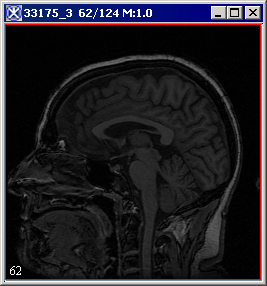

The algorithm begins to run and the Registering Images window appears with the status. When the algorithm stops running the registered image appears in a new image frame. Refer to Figure 4.